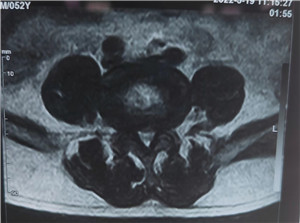

3、腰椎管狭窄症:在腰椎,椎体前缘的骨刺一般也不容易导致什么症状;关节突关节的骨刺、结合黄韧带肥厚、椎间盘突出,以及椎体之间的不稳定,可以导致腰椎管狭窄症的症状,严重者甚至可以出现腰椎的退变性滑脱。